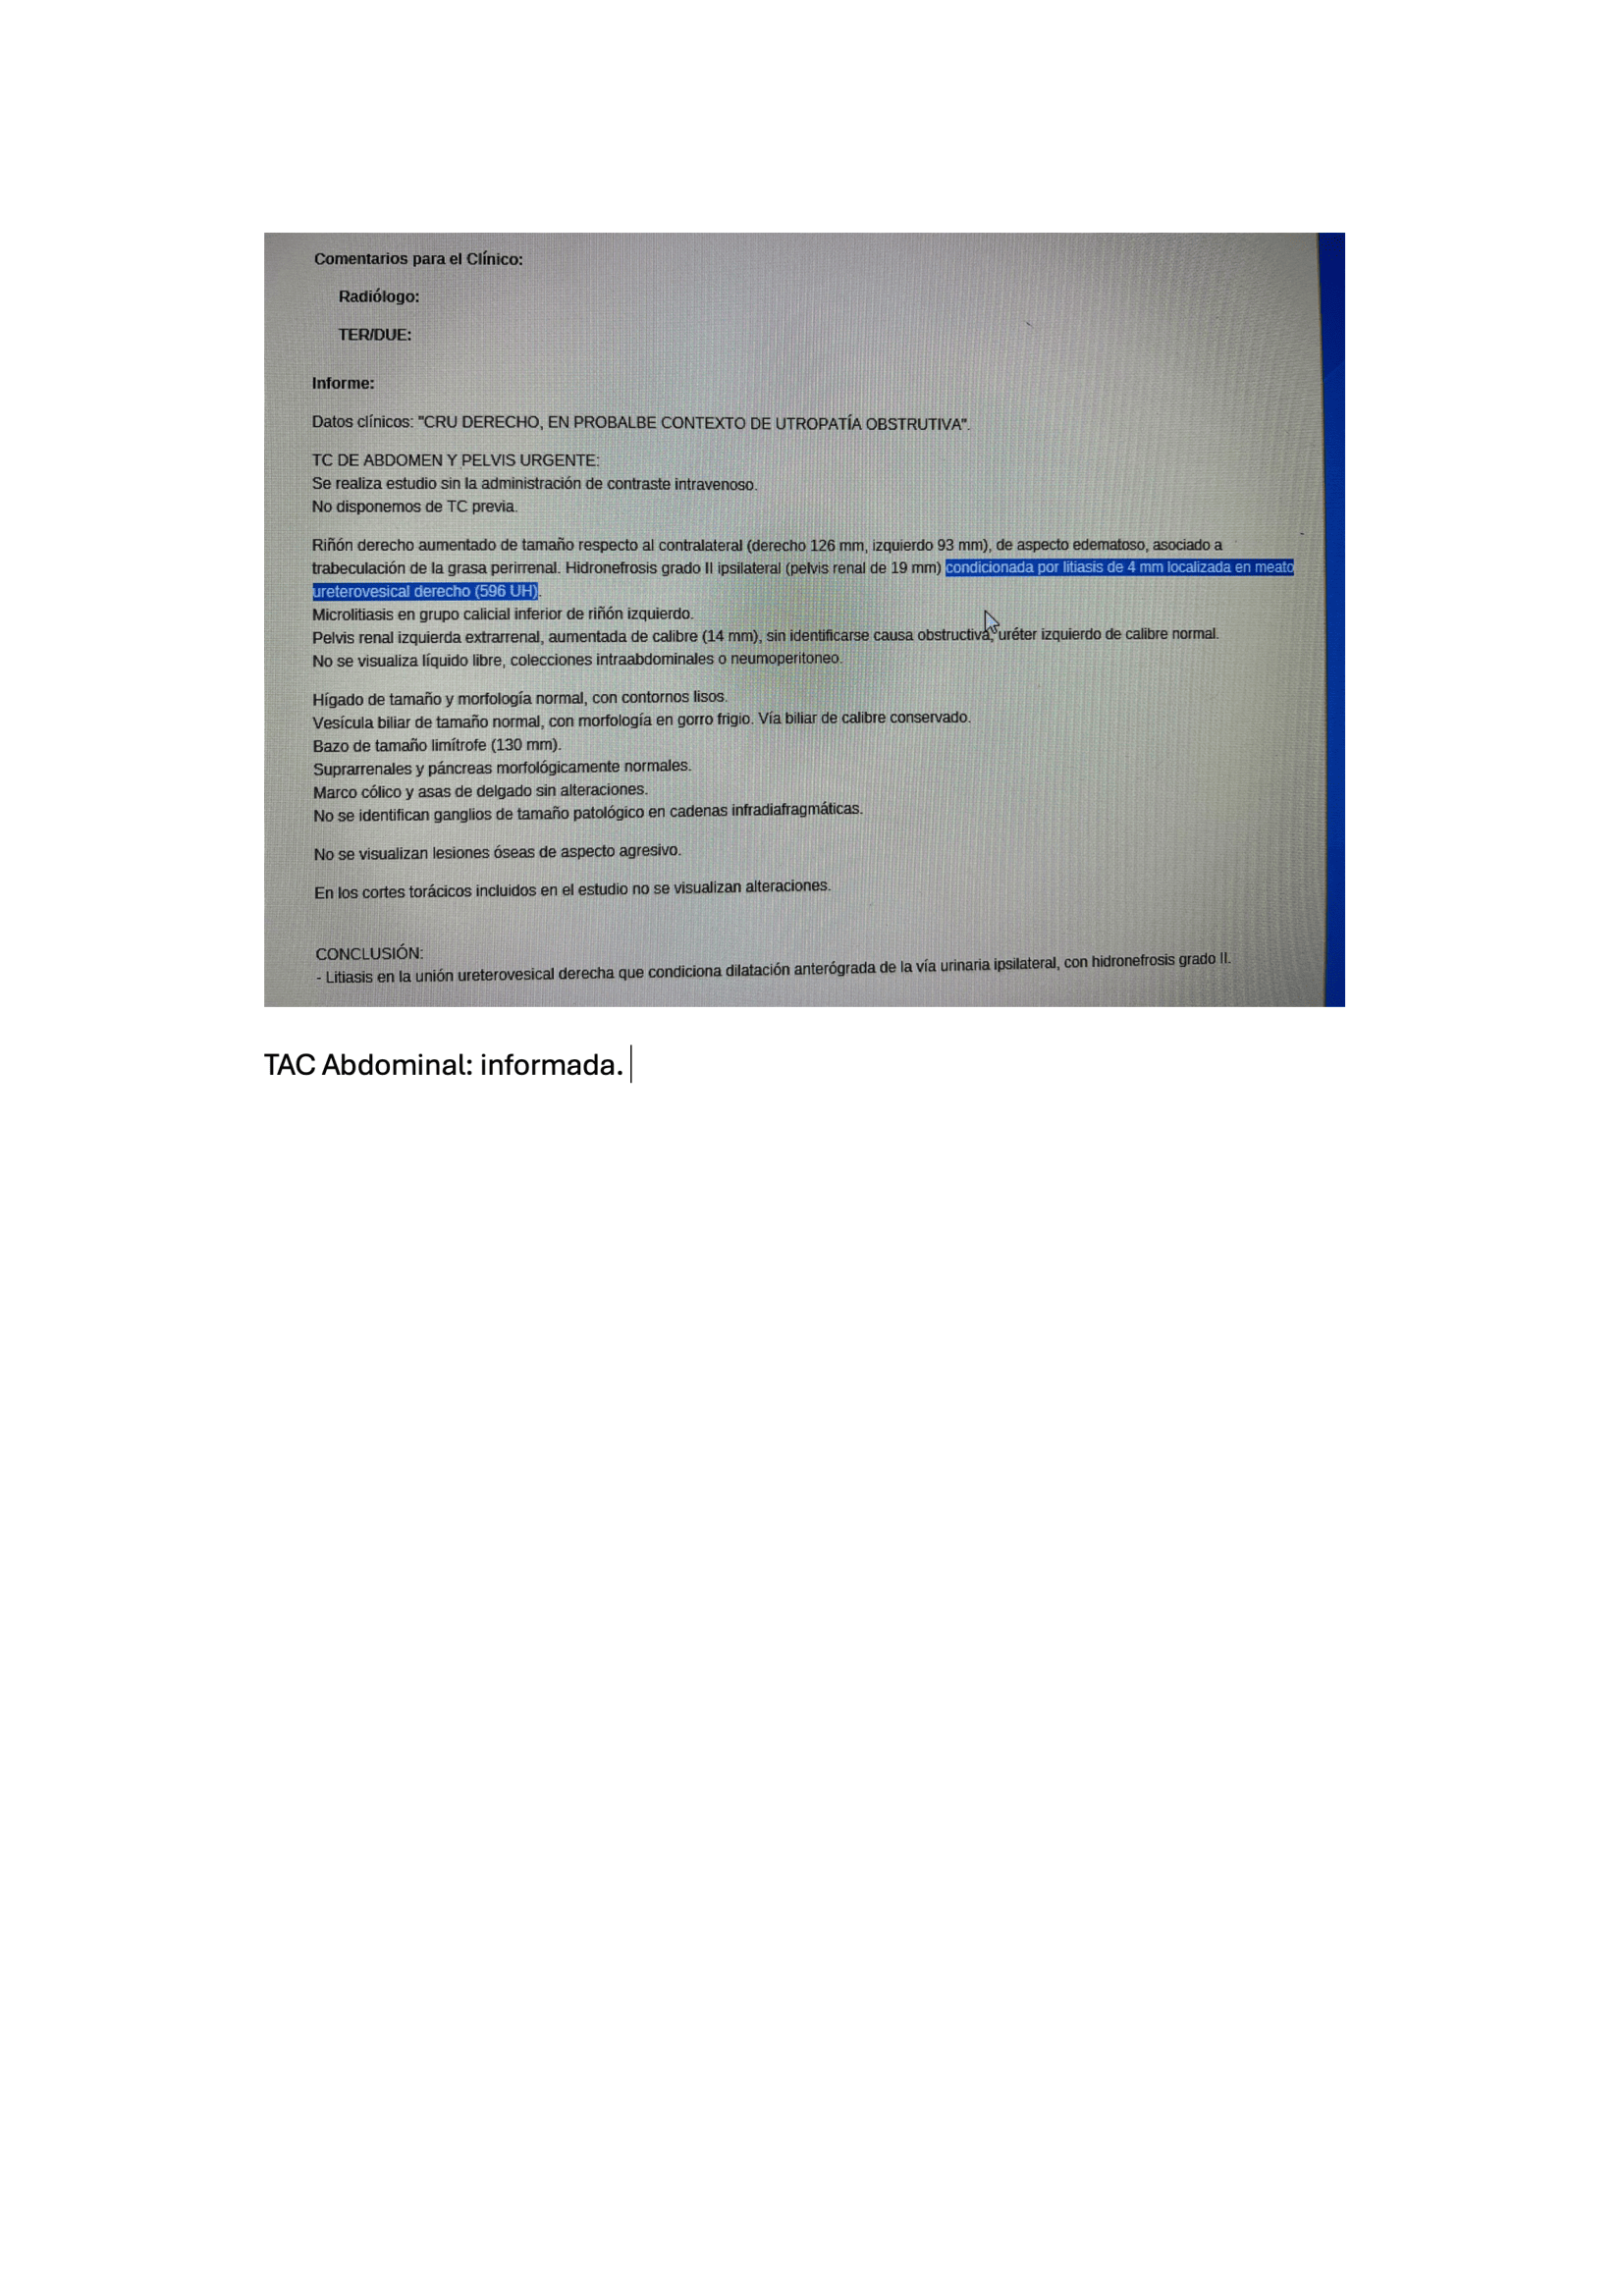

Exploración física, fiebre (39,5 °C) y taquicardia (FC: 120), puño-percusión positiva en la fosa lumbar derecha, sugiriendo una patología renal. Se realiza POCUS) que revela un riñón derecho aumentado de tamaño con una imagen lítica compatible con un cálculo renal de 1,2 cm x 8 mm, junto con dilatación de la pelvis renal (hidronefrosis grado I-II). Una tomografía computarizada (TAC) confirma los hallazgos y muestra un cálculo renal de 4 mm en la zona vesicoureteral distal, no obstruyendo totalmente la vía urinaria.

- Antibioticoterapia (Ceftriaxona 2 g + Amikacina 1 g cada 24 horas por 48 horas) posterior se dejó tratamiento ambulatorio con Amoxicilina/Ácido clavulánico por 7 días + Tamsulosina 0,4 mg cada 24 horas + Metamizol cáp. 575 cada 8 horas,cita con urología en 30 días.

Urología: evidencia mejoría del cuadro clínico, niega fiebre, dolor. Refiere expulsión de pequeño cálculo tras 5 días de tratamiento. Ecografía, Riñón de tamaño normal, homogéneo, se evidencia imagen litiásica que deja sombra acústica posterior de 1,2 cm x 9 mm aprox. que no compromete vía urinaria, no dilatación de pelvis renal. Se deja tratamiento con tamsulosina durante 3 meses hasta nueva valoración. Control con su médico de familia, solicitar seguimiento de niveles ácido úrico y si alteración pautar tratamiento.